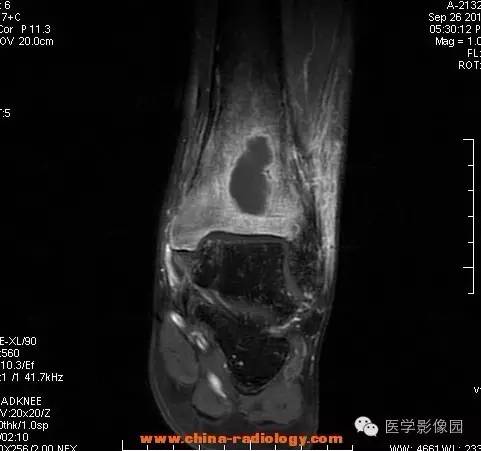

【病例】胫骨骨脓肿1例MR影像表现

影像学表现:胫骨中下段干骺端不未规则形长T1长T2信号,T2WI见不完整环形稍低信号影,T2脂肪抑制低信号更明显,并见胫骨下段及踝关节后外侧软组织呈弥漫稍高信号,增强明显不均匀强化,增强见低信号环内有环形强化影。

影像学表现:表现为长骨干骺端有椭圆形密度减低区,边缘有清晰的骨质硬化,病变与邻近正常骨髓腔境界清楚。MRI上T1WI呈低信号,少数呈等信号,T2WI多为混杂高信号,增强扫描可见环状强化,强化的脓肿壁薄而均匀。